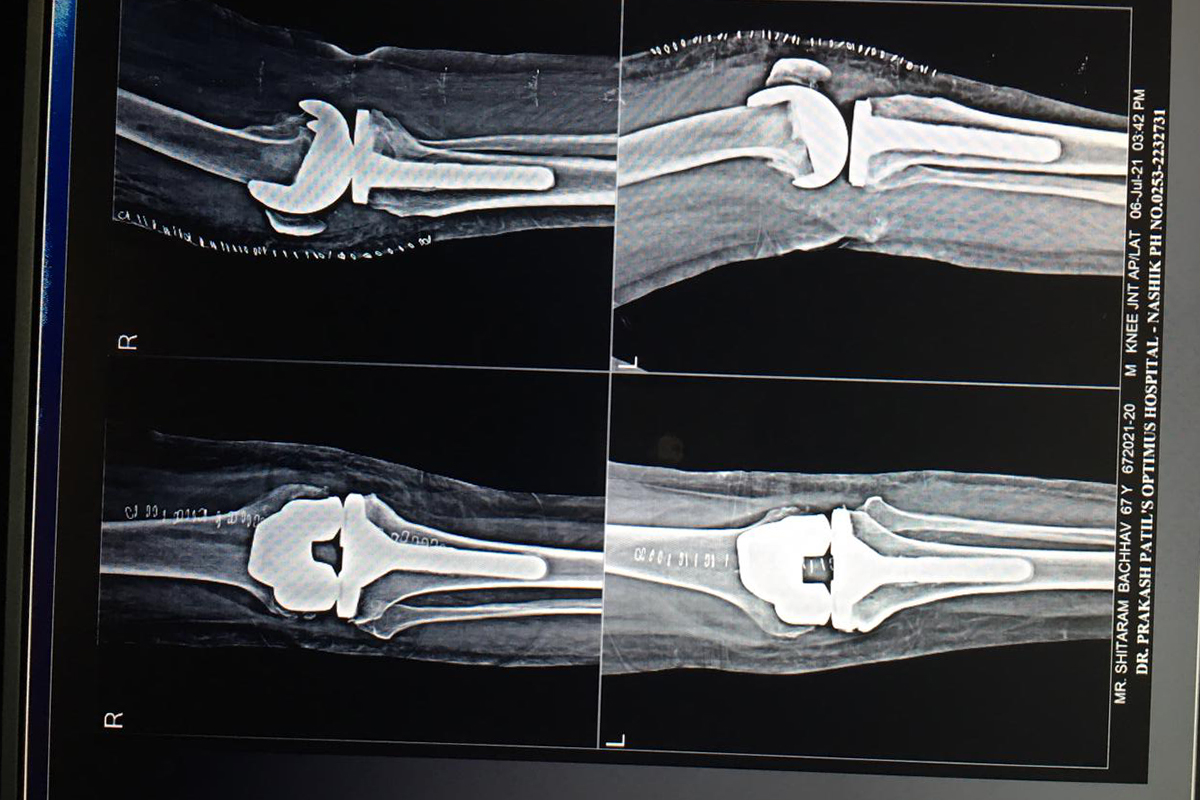

Joint Replacement

Photo Gallery